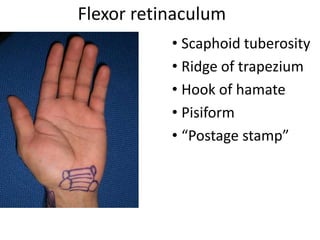

- Naming the bones, joints, tendons, nerves and skin landmarks of the hand and wrist.

- It describes flexor tendon zones, extensor compartments, and pulley system anatomy.